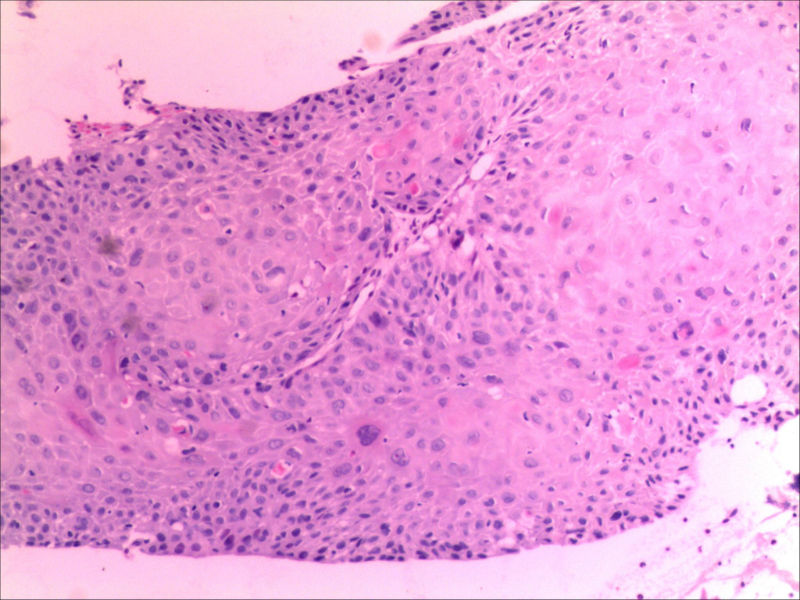

食管活检男64岁食管粗糙

图4